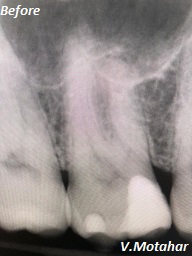

Root Canal Treatment on a molar teeth which had deep decay!

before

after